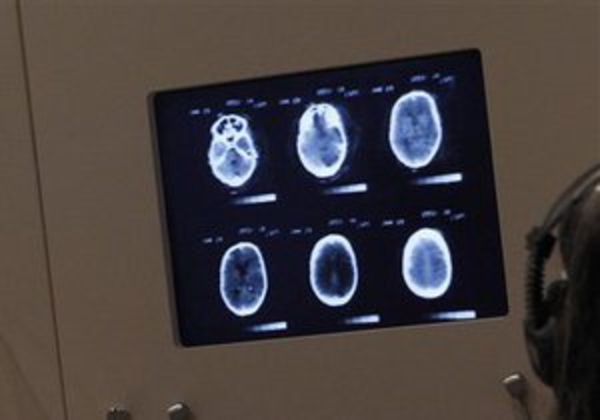

Группа ученых из Национального института радиологии в Чибе (Япония), проследила за работой некоторых областей мозга, связанных с работой сознания и самооценки человека.

Ученые обратили внимание на то, что фронтальная кора и полосатое тело в мозге человека содержат необычно большое количество нейронов, способных "считывать" молекулы допамина, гормона удовольствия.

Обычно допаминовые рецепторы размещены в центре удовольствия и тех областях мозга, которые связаны с проявлением эмоций. Ученые предположили, что обнаруженная ими цепочка нервных клеток может быть связана с чувством самооценки и синдромом "ложного превосходства".

Для проверки гипотезы ученые собрали группу из 24 добровольцев-мужчин, проанализировали число допаминовых рецепторов и их активность в мозге, а также попросили их пройти соцопрос. В частности, биологи интересовались, насколько оптимистично участники эксперимента смотрят в будущее, как оценивают себя и что думают о своей социальной привлекательности.

В итоге выяснилось, что люди с высокой самооценкой обладали небольшим числом допаминовых нейронов, а депрессивные участники с комплексом неполноценности - множеством таких клеток.

Ученые пришли к выводу, что данная цепочка нейронов напрямую влияет на самооценку и является причиной развития чувства ложного собственного превосходства.